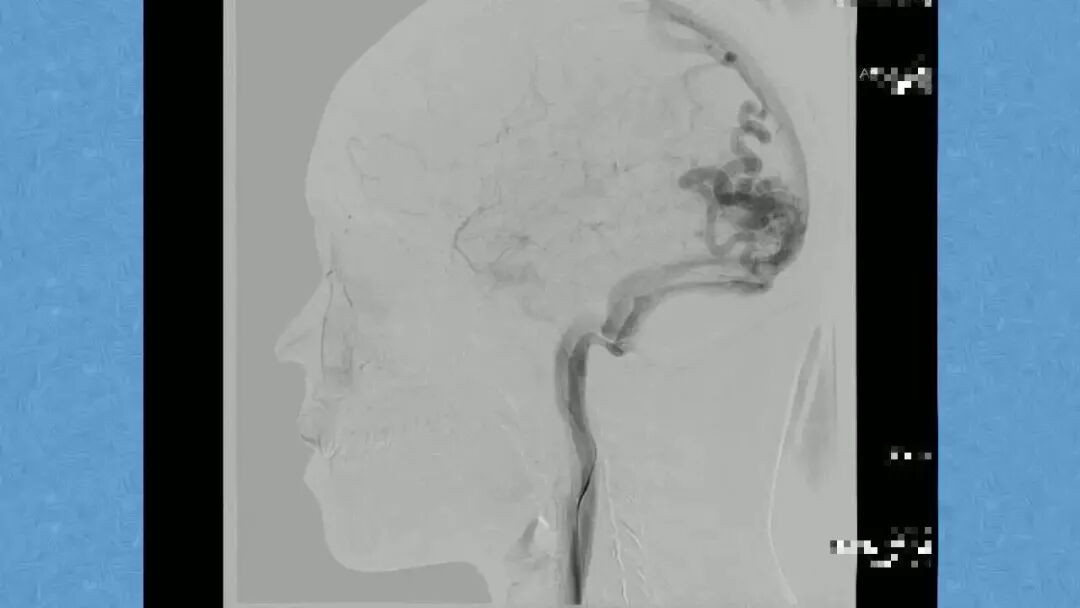

今天为大家分享的是《贝朗时间》第二十九期,湖北十堰市太和医院神经外科张力教授团队带来的:一个AVM患者的48小时纪实,欢迎阅读、分享!

张力教授:AVM切除术